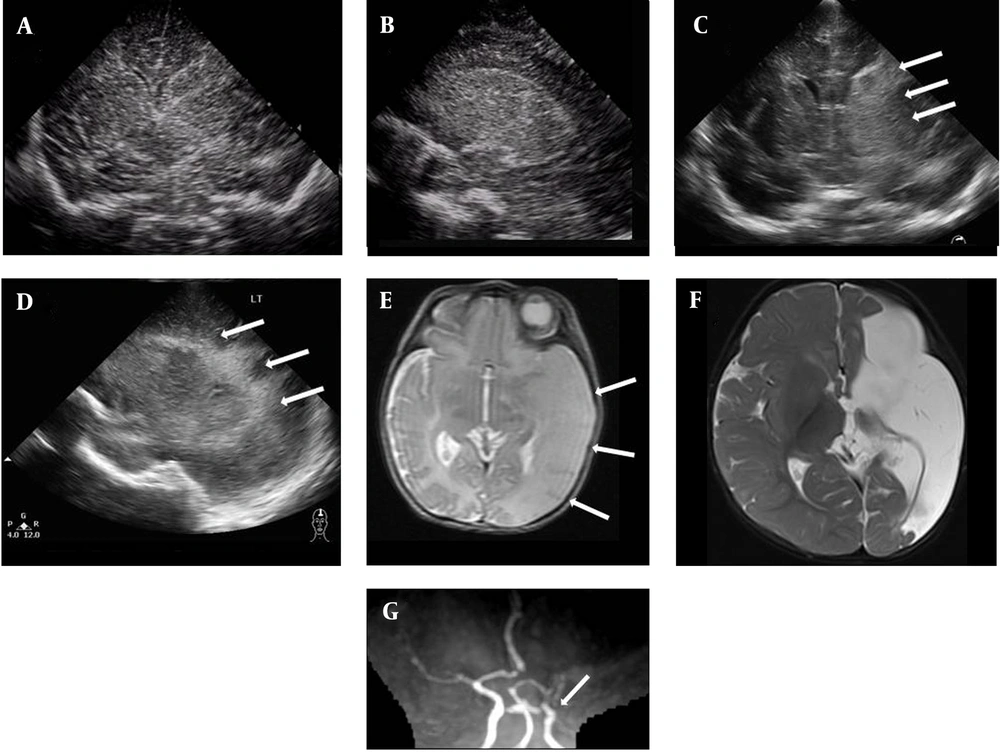

A 1-day-old male neonate was born at 37 weeks’ gestation via cesarean section due to breech presentation. He weighed 2225 g (10-25th percentile), was 48 cm in length (50-75th percentile), and had a head circumference of 33 cm (50th percentile). Apgar scores were 6 and 8 at 1 and 5 minutes, respectively. Maternal hypertension developed 2 weeks before delivery and was treated. After birth, delayed initial crying and cyanosis were noted. Resuscitation was done and the infant was hospitalized for observation. On physical examination, weak sucking and breath holding while crying were noted. Cranial ultrasound on day 3 revealed very mild increased echogenicity over the left thalamus, basal ganglia and periventricular area with ventricular compression (Figure 1). Decreased right upper and lower limb movements were observed on day 4 of life. Repeated cranial ultrasound on day 5 of life revealed more echogenicity over left thalamus, basal ganglia and periventricular area (Figure 1). For further evaluation, magnetic resonance imaging (MRI) and magnetic resonance angiography (MRA) with diffusion-weighted imaging (DWI) were performed on day 5 of life. The T2-weighted brain MRI (T2WI) showed high signal intensity (SI) over the left fronto-parieto-occipital cortical and white matter areas. MRA showed flow reduction over the left MCA branch (Figure 1). Middle cerebral artery (MCA) infarction was diagnosed. Pre-Wallerian degeneration was also noted on DWI, with high SI over the left posterior limb of internal capsule (PLIC), cerebral peduncle and basis pontis (Figure 2).

The patient developed spastic hemiplegia in the following months. MRI performed when he was 8 months of age revealed multicystic encephalomalacia and Wallerian degeneration (Figures 1, 2).

The most common feature of PAIS is seizures, accounting for 70-90%. Additional signs are apnea/cyanosis, lethargy, feeding difficulties, hypotonia and tone asymmetry. However, some infants remain asymptomatic (1). Cranial ultrasound (CUS) is the primary modality of examination when a neonate is suspected to have neonatal encephalopathy. However, it is operator dependent. In one study, the sensitivity was 68% in the first 3 days and 87% from day 4 to day 14 (2). In this index case, the echogenicity was not apparent until day 5 of life (Figure 1), so repeated sonographic follow-up was required.

MRI is the gold standard for diagnosing PAIS. In this index case, the infracted area on T2WI showed reduced contrast with the white matter, which may be due to increasing brightness of the infracted area, leading to absence of cortex (the so-called ”missing cortex sign”). MRA of the head provides visualization of great arteries but not small vessels. Carotid dissection is rarely detected in neonates and is associated with birth trauma (3), so a neck MRA may sometimes be needed. In our case, MRA showed asymmetry with reduction in flow through the left MCA and its branches (Figure 1), which was compatible with MCA infarction.

ultrasound scan on day 3 (A, B) and day 5 (C, D) of life with coronal and left parasagittal views showed increased echogenicity over the thalamus and basal ganglia. The echogenic area was more apparent on day 5 than day 3 of life (arrow). On day 5 of life, T2WI showed left MCA territory infarction with a “missing cortex sign” (E) (arrow), and MRA showed flow reduction in the left MCA (G) (arrow). Multicystic encephalomalacia was demonstrated on T2WI when the patient was 8 months old (F).